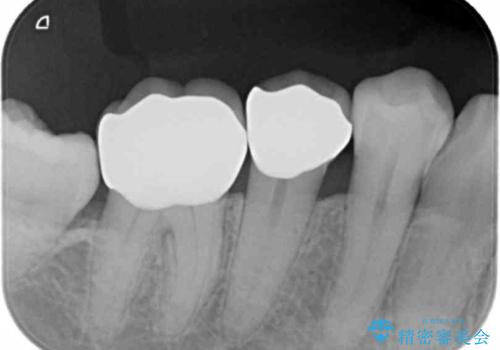

詰め物の下が虫歯 つぎはぎの歯をしっかり治療

- 虫歯治療で来院。

詰め物の下が虫歯になっていました。

虫歯をしっかりとった後、セラミックで修復しました。

詰め物の下の虫歯は特に奥歯は大きかったのですが、神経を取らずに済みました。